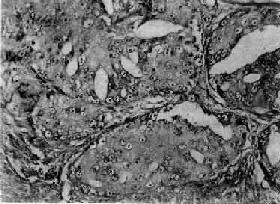

二、前列腺癌前列腺癌(carcinoma of prostate)多发生于60岁以上的老年人,在我国远较欧美国家少见。美国报告前列腺癌的死亡率占恶性肿瘤死亡率的第二位,在我国前列腺癌的发生率只占恶性肿瘤的0.3%左右。 【病因】 前列腺癌的病因尚不十分清楚,一般认为激素特别是雄激素可能起重要作用。长期以来各家对前列腺癌与前列腺增生之间的关系看法不一。目前大多数学者认为两者间无明显关系,因为前列腺癌很少发生于良性增生的前列腺内。在组织发生上增生与癌的发生部位也不相同,前列腺增生多发生于尿道周围部的前列腺组织(即前列腺内区);而前列腺癌几乎都开始发生于前列腺的包膜下部(即前列腺外区),该部组织对雄激素敏感,高水平的雄激素可使该部增生。据统计,阉人不发生前列腺癌,这些都支持雄激素和前列腺癌有关。但前列腺癌患者多为老年人,睾丸产生的雄激素已经降低,所以仍有不支持此说的根据。有人假设前列腺癌发展很慢,可以长期处在潜伏状态,可能在雄激素尚处于较高水平时即已发生小的癌灶,发展到老年才出现症状,这一假设尚有待进一步验证。 【病变】 肉眼观,前列腺癌初期为单个或多数的硬结节,其前列腺可以增大,也可正常大小。早期病灶几乎都发生于包膜下,其中大多数发生于后叶,其次是两侧及前叶的包膜下,而发生于中叶者极为少见。晚期肿瘤可扩展到全部前列腺,使前列腺明显增大而质地变硬。切面灰白色夹杂以多少不等的纤维性条纹或间隔,也可呈均质性夹以不规则的黄色区域。 镜下,97%的前列腺癌均为腺癌,少数为移行细胞癌和鳞状细胞癌。依其分化程度可分为高分化、中分化和低分化3型。高分化前列腺癌最多见,癌细胞排列成大小不等的腺样结构,颇似前列腺增生腺体,但癌细胞体积较小,核较深染,上皮细胞往往呈多层排列并较不规则(图14-4),有时可呈乳头状腺癌或腺泡腺癌结构,并常可见癌组织向间质浸润生长;中分化腺癌全部或部分呈腺样结构,但腺体排列较紊乱,核异型性较明显,且有时形成筛状结构;低分化腺癌的癌细胞一般较小,排列成实体团块或条索,腺腔样结构很少(图14-5)。多数病例乃由上述多种组织结构混合组成。

图14-4 前列腺癌(高分化型) 腺体密集,癌细胞体积较小,核深染,上皮细胞呈多层排列并较不规则,可见间质浸润